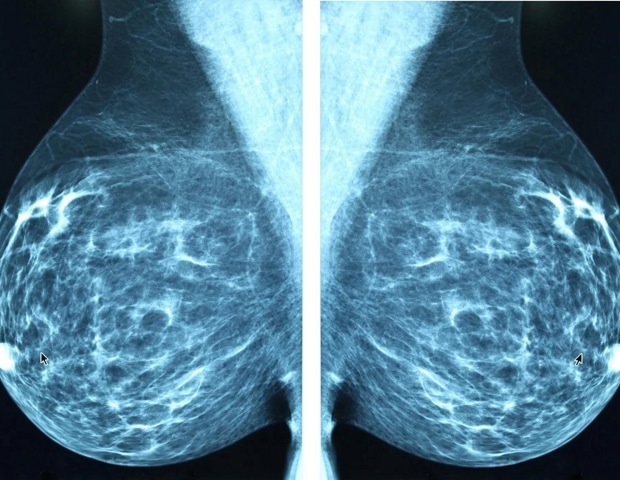

Исследование, проведенное исследователями из Научно-исследовательского института больницы Дель-Мар, приближает одну из наиболее важных вех в лечении рака молочной железы, делая иммунотерапию эффективной против наиболее распространенного типа опухоли: эстроген-позитивного или просветного рака молочной железы. На этот подтип приходится 70% случаев рака молочной железы, и, несмотря на эффективное лечение, он является причиной самой высокой смертности от общего числа случаев. Кроме того, иммунотерапия не эффективна и не одобрена, поскольку она не демонстрирует реакции иммунной системы на эти опухоли, за исключением подгруппы меньшинства, которая как раз имеет низкие уровни рецепторов эстрогена. Работа опубликована в журнале «Журнал клинических исследований» и возглавляется командой доктора Тони Селиа-Террасса из лаборатории динамики раковых стволовых клеток и метастазов Исследовательского института больницы дель Мар. Исследование поддерживается Ausonia через Испанскую ассоциацию по борьбе с раком.